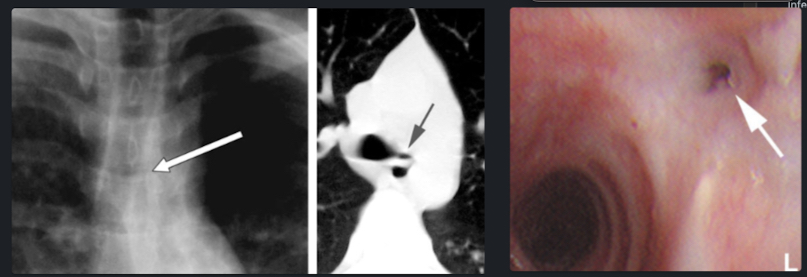

Sténose Post Transplantation

Général

- Sur le site de l’anastomose

- Les artères bronchiques ne sont pas rétablies post-transplant → dépendance du réseau artériel pulmonaire (collatérales rétrograde)

- De Nos jours risque d’environ 15%

- TTT: Dilatation, Stent